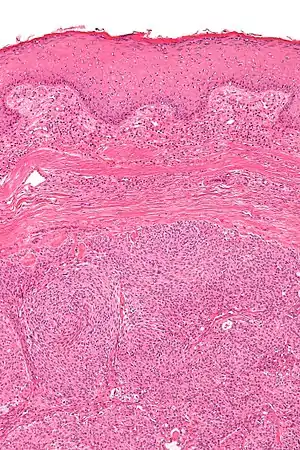

| Micrograph showing an acrospiroma. H&E stain. | |